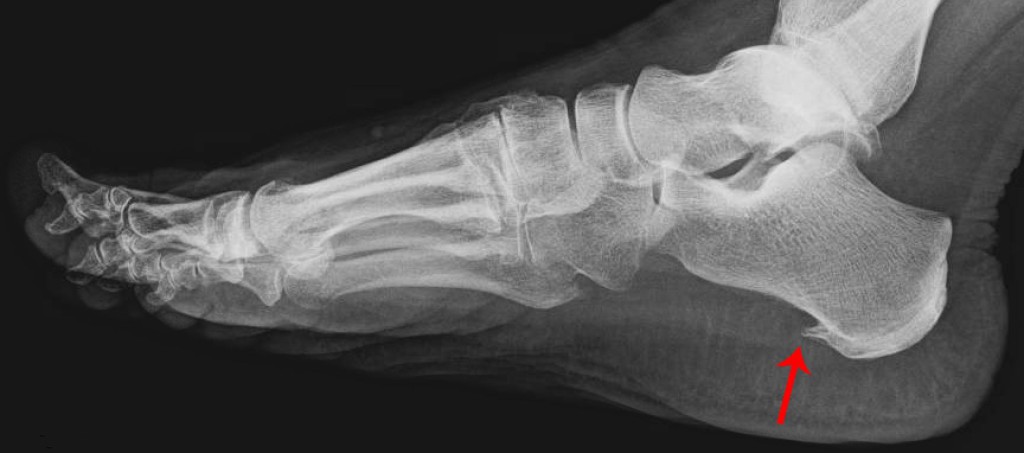

На рентгеновских снимках пяточная шпора выглядит как шиповидный нарост на пятке. Основные причины ее появления включают:

Болевые эпизоды чаще всего наблюдаются утром. В течение дня они могут утихать, но к вечеру снова усиливаются. Если состояние не лечить длительное время, боль может прогрессировать и беспокоить даже в состоянии покоя. В некоторых случаях пациенты не могут передвигаться без помощи костылей, так как наступать на ногу становится крайне неприятно. Основной причиной таких ощущений является хроническое воспаление. О наличии шпоры можно предположить только по симптомам, а для точной диагностики рекомендуется провести рентгенологическое исследование.